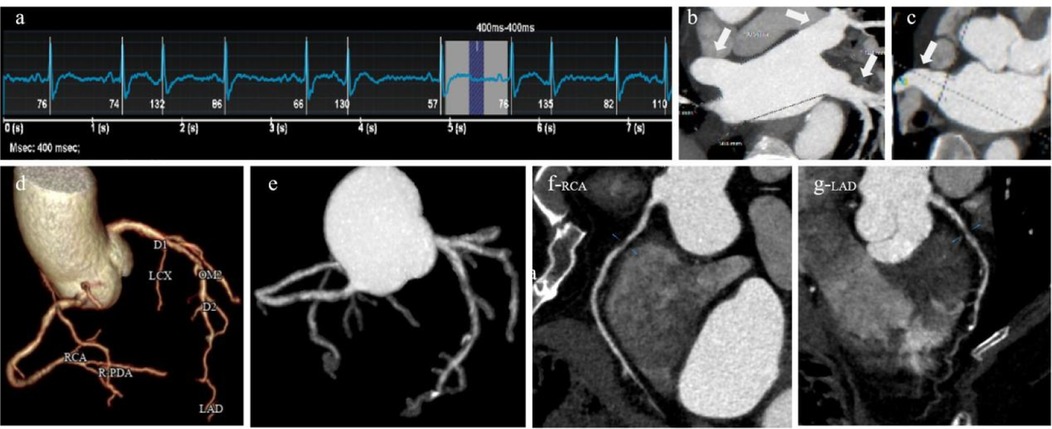

Figure 1

A 61-years-old atrial fibrillation patient. (a) ECG showed a heart rate of 82 beats/min and heart rate variability of 80 beats/min during the scan, (b) pulmonary vein, MIP, (c) left atrial appendage, MIP, (d) coronary artery tree, 3D-VR, (e) coronary artery tree, 3D-MIP, (f) right coronary artery, CPR, (g) left anterior descending coronary artery, CPR.